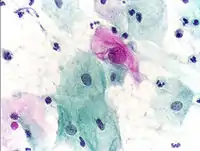

Micrograph of a Pap test showing a low-grade intraepithelial lesion (LSIL) and benign endocervical mucosa. Pap stain.

The sample is stained using the Papanicolaou technique, in which tinctorial dyes and acids are selectively retained by cells. Unstained cells cannot be seen with a light microscope. Papanicolaou chose stains that highlighted cytoplasmic keratinization, which actually has almost nothing to do with the nuclear features used to make diagnoses now.

Pap tests commonly look for epithelial abnormalities/ metaplasia/ dysplasia/ borderline changes, all of which may be indicative of CIN. Nuclei will stain dark blue, squamous cells will stain green and keratinised cells will stain pink/ orange. Koilocytes may be observed where there is some dyskaryosis (of epithelium). The nucleus in koilocytes is typically irregular, indicating possible cause for concern; requiring further confirmatory screens and tests.